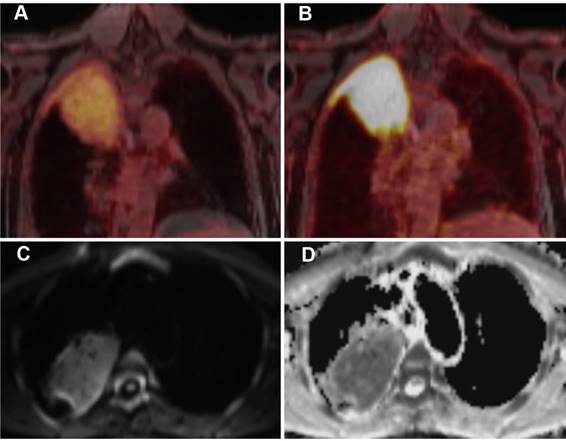

Figure 3

A 63-year-old patient with MALT lymphoma in the upper lobe / apex of the right lung and adjacent pleura. The lymphoma presents as a large consolidation with strong diffusion restriction (high signal on the DWI image (C) and low signal on the corresponding ADC map (D)). On PET, the lymphoma shows only a moderate uptake of [18F]FDG (A), indicating moderately increased glucose metabolism, but a strong uptake of [68Ga]Ga-Pentixafor, suggesting a high CXCR4 expression (B).